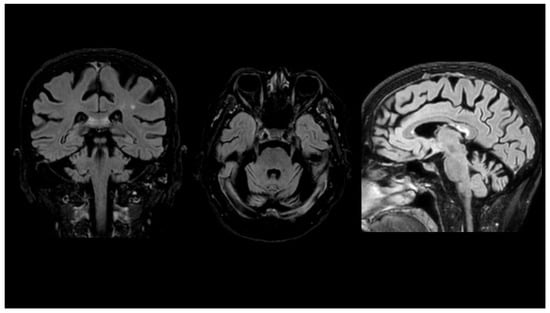

3. Case Report